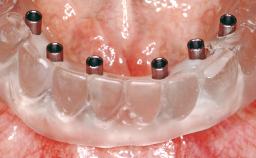

Immediate Loading of Six Implants in the Maxilla and Final Restoration with a Full-Arch CAD/CAM Zirconia FDP

A 63-year-old male patient was referred for a consultation and treatment of partial edentulism in the maxilla. The patient presented with residual anterior teeth and declined a partial removable prosthesis. He reported that the maxillary posterior teeth had been extracted due to mobility and periodontal disease two months before the consultation. The patient’s chief complaint was that his residual maxillary teeth were mobile and that he was unable to chew. The patient’s desire was a stable and comfortable fixed maxillary rehabilitation. The patient was a light smoker (fewer than 10 cigarettes/ day), and his medical history was without significant findings. He was not on any regular medication at the time of consultation. The extraoral examination revealed a normal physiognomy with a correct distribution of the facial thirds. The patient presented a low lip line, and the transition line between teeth and soft tissues was not exposed during a forced smile.

Prosthesis Type FDP

Loading Protocol Immediate